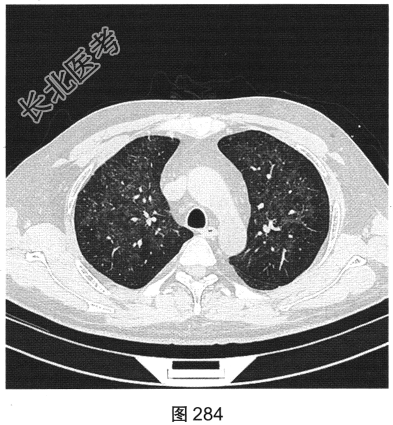

- [材料题] 患者男性,33岁,因“双下肢散在皮下出血点伴尿检异常3个月余,咳嗽、胸闷伴发热一周”就诊。患者脂肪肝、胆囊炎,服用莲葡双清片;随后几日内食用淡水鱼、鱿鱼、饮啤酒;5天后出现双下肢散在皮下出血点,未重视;10天后出现腹痛,在当地医院检查尿中有蛋白、定量不详,血常规检查正常,肾功能正常,应用醋酸泼尼松效果欠佳,行肾活检术,病理诊断:紫癜性肾炎,继发IgA肾病。患者每天静脉滴注甲泼尼龙0.5g,共3天,后改为口服甲泼尼龙28mg/d,共35天。一周前着凉后出现咳嗽、胸闷伴发热,体温达39.1℃,于当地医院抗炎治疗效果欠佳,遂来本院。实验室检查:血白细胞计数6.92×109/L,中性粒细胞0.845,CRP为2.7mg/dl。患者PP65阳性。胸部CT检查如图284~图287所示。

- 多项选择题1.患者的主要影像特征是( )

A、双下肺为著

B、伴细网格影

C、血管支气管束增厚

D、小叶中央结节

E、以磨玻璃密度为主

F、双肺弥漫分布